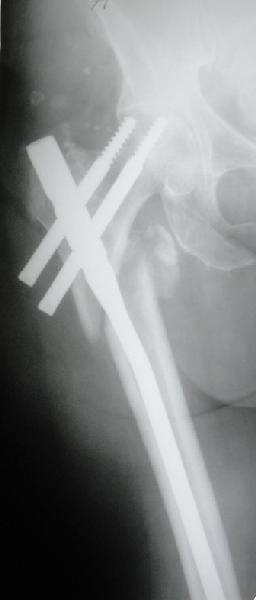

Перелом тут больше подвертельный. Нагрузка без торцевого упора на уровне перелома привела к телескопированию отломков на стержне. Ну и варус небольшой тоже свою лепту внес - если бы его не было, контактирующие латеральные стенки обоих отломков предотвратили бы укорочение, да и срослось бы за пару месяцев. А раз не срослось, упора отломков нет, более слабым местом оказались не нижние винты, а кость в головке и шейке. Так что надо было хотя бы удалить нижние винты до начала полной нагрузки.

На мой взгляд, причиной телескопирования явилось несоответствие диаметра гамма нэйл с диаметром канала подвертельного отдела бедра: обратите внимание на величину протрузии шеечного винта и величину медиализации дистального фрагмента - они одинаковы, смещение или телескопирование фрагментов происходило до того момента, пока гамма нэйл не упёрся в медиальный кортекс и образовалось пространство между латеральным

кортексом и латеральной поверхностью гвоздя.

Здраствуйте. По данному снимку видно 2-а основных момента которые привели к протрузии винта в вертлужную впадину: 1) шеечный винт дистальной поверхностью наружнего края "зацепился" за латеральный кортикал бедра, это не дало сработать динамической системе гвоздь-винт. 2) лучьше шеечный винт проводить ближе к дуге Адамса, там болееплотная костная ткань. Решенее: как подготовка к эндопротезированию, реостеосинтез, можно такой же системой, но с учетом упомянутых моментов, максимальное безнагрузочное ЛФК (без боли).